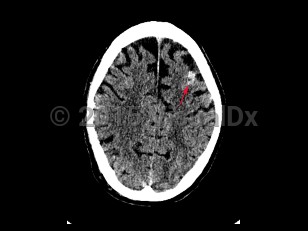

Subarachnoid hemorrhage (SAH) is bleeding directly into the cerebrospinal fluid (CSF) within the subarachnoid space that surrounds the brain. It usually presents as a severe sudden-onset headache, often described as the worst headache of the patient's life, with radiation of pain down the neck and back. Onset of headache may be accompanied by a brief loss of consciousness, nausea, vomiting, and meningismus. SAH occurs in about 10 per 100 000 people per year. Incidence increases with age and peaks in the sixth decade of life. Risk factors include female sex, smoking, alcohol use, drug abuse, hypertension, oral contraceptive use, known cerebral vascular malformation, collagen vascular disease, and family history of SAH. In the United States, African Americans are at higher risk.

Cerebral aneurysms > 5-7 mm are most likely to rupture. Approximately 1%-3% of patients visiting the emergency department for a headache are subsequently found to have a SAH. Trauma is the most common cause of SAH; however, nontraumatic SAH is found to result from a ruptured saccular aneurysm in 80% of cases. Patients with SAH require close monitoring and often require intensive care unit admission.